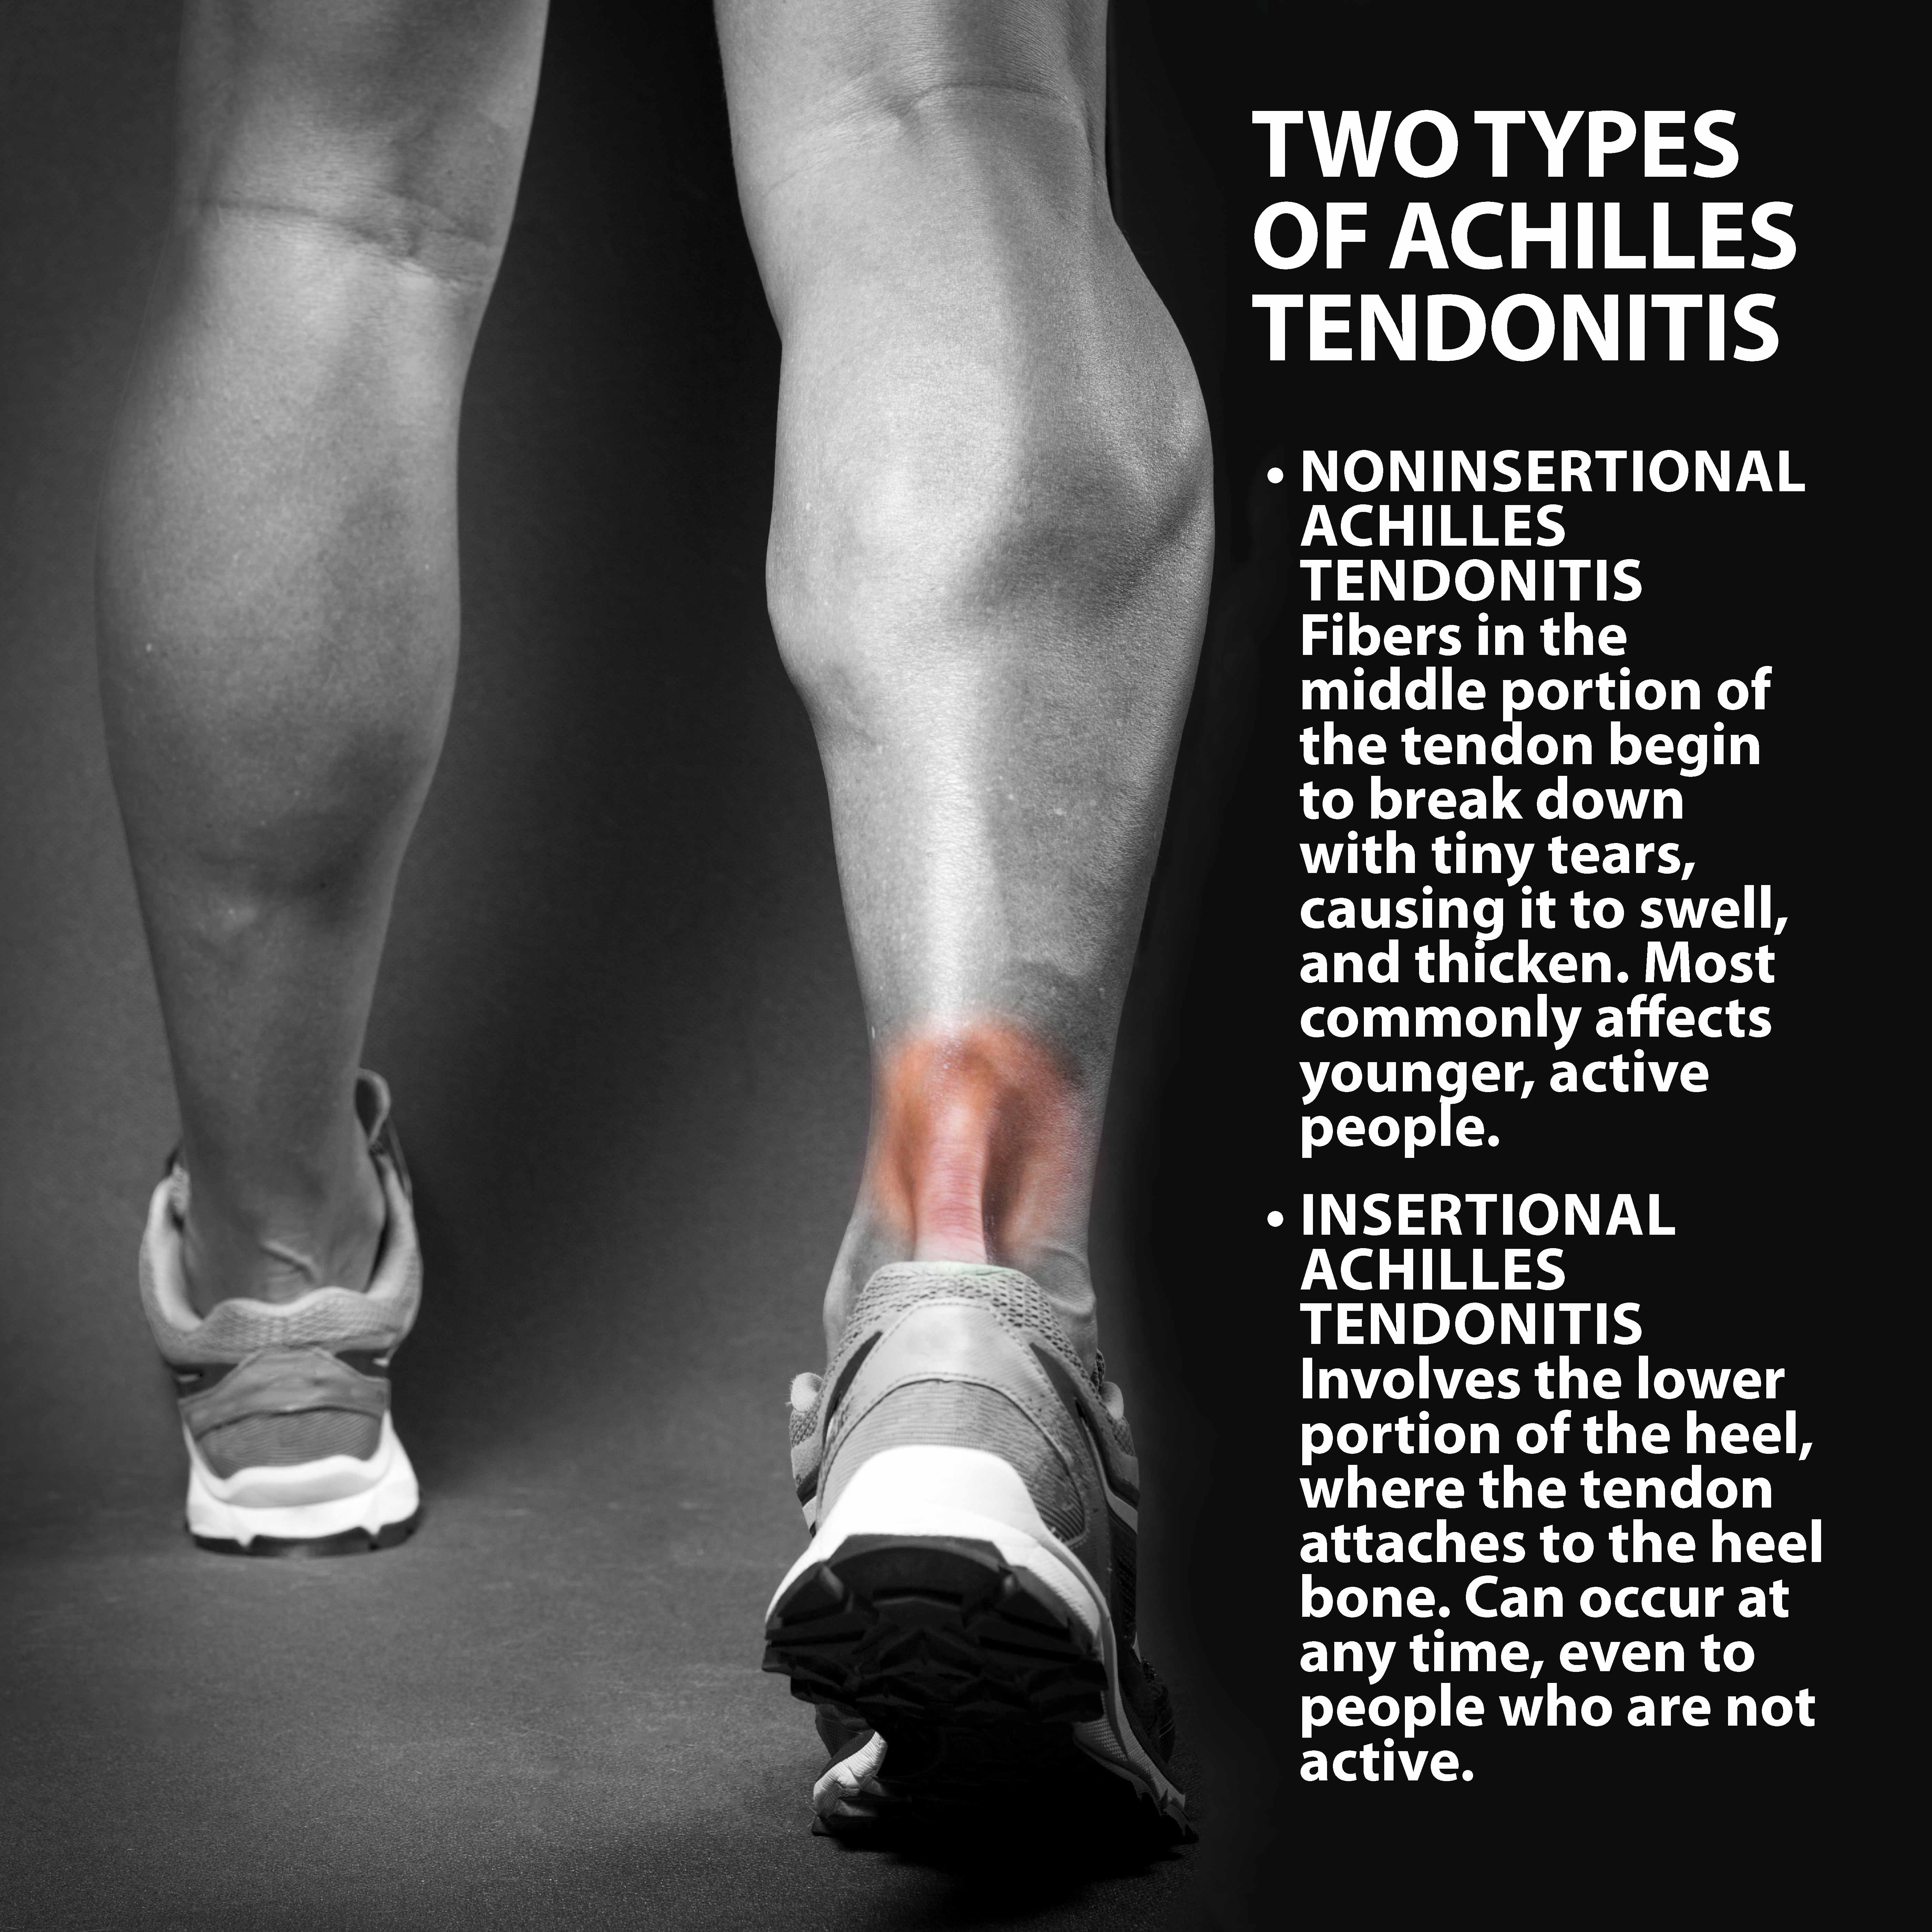

Achilles Tendonitis Basics | Florida Orthopaedic Institute

Feel Better Now Series – How To Treat Achilles Tendinitis – Best home …